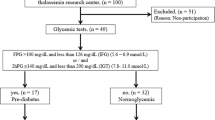

Figure 1 shows Line chart of the differences in mean carotid IMT based on the severity of iron loading at different age groups. These differences are lower in the younger patients and increase with relatively exponential curve in the older patients.